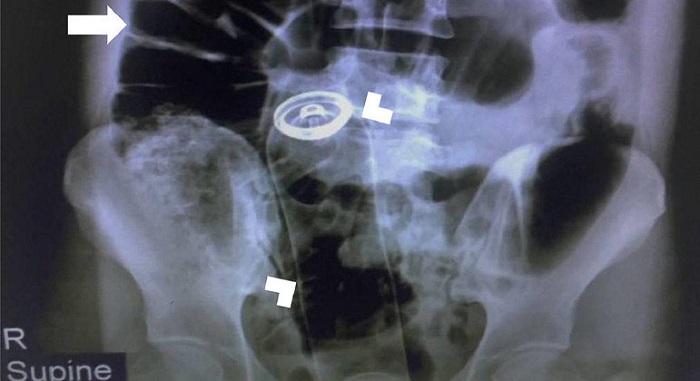

Foi feito um exame de radiografia que mostrou o objeto. O cólon, parte seguinte ao reto, aparecia dilatado na imagem.

Imediatamente, o paciente foi encaminhado para o centro cirúrgico e submetido a uma laparotomia, procedimento que envolve uma incisão da parede abdominal para obter acesso à cavidade abdominal.